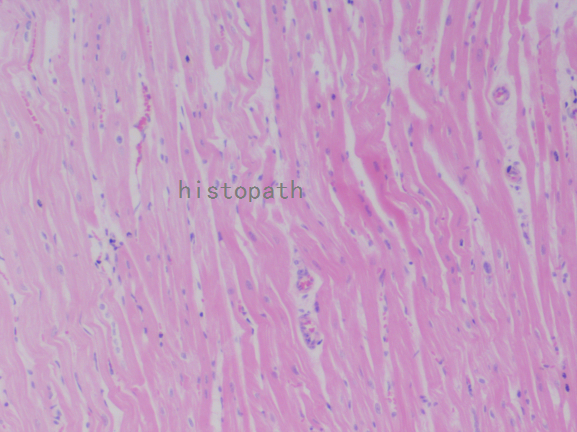

苏木精--伊红染色法(hematoxylin-eosin staining),简称HE染色法,石蜡切片技术里常用的染色法之一。苏木精染液为碱性,主要使细胞核内的染色质与胞质内的核酸着紫蓝色;伊红为酸性染料,主要使细胞质和细胞外基质中的成分着红色。HE染色法使组织学、胚胎学、病理学教学与科研中最基本、使用最广泛的技术方法。

染色结果:

细胞核呈蓝色,细胞质、肌肉、结缔组织、红细胞、嗜曙红颗粒呈不同程度的粉红色。钙盐、软骨基质和各种微生物也可染成蓝色或紫蓝色。核仁呈红色。着色情况不仅与组织或细胞的种类有关,也随其生活周期及病理变化而改变。质量优良的HE染色切片样本,细胞核与细胞质蓝红对比明显,胞核鲜明,核膜及核染色质颗粒均清晰可见。